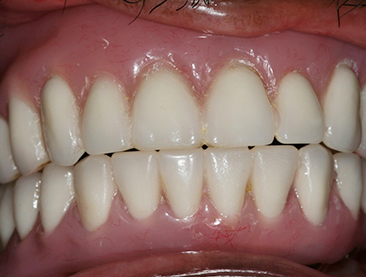

Fully edentulous clinical cases